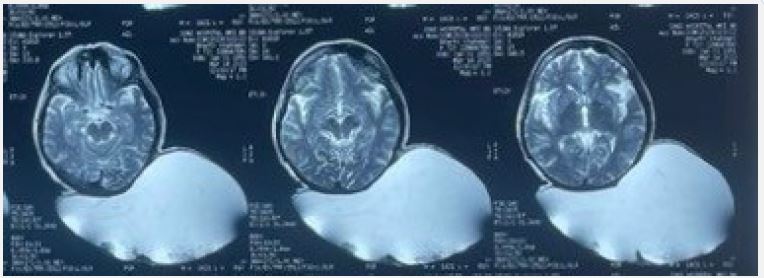

On preoperative Magnetic Resonance Imaging (MRI), a large cystic lesion was detected in the scalp region between the parietal and occipital lobes. The lesion was well-defined, had multiple compartments, and measured around 26×24×12 cm. The cystic lesion did not affect the skull or brain. On T2-weighted images, the lesion appeared homogeneous with a high-intensity signal (Figure 3).

Figure 3: T2 WI-Magnetic resonance image-Axial cuts.